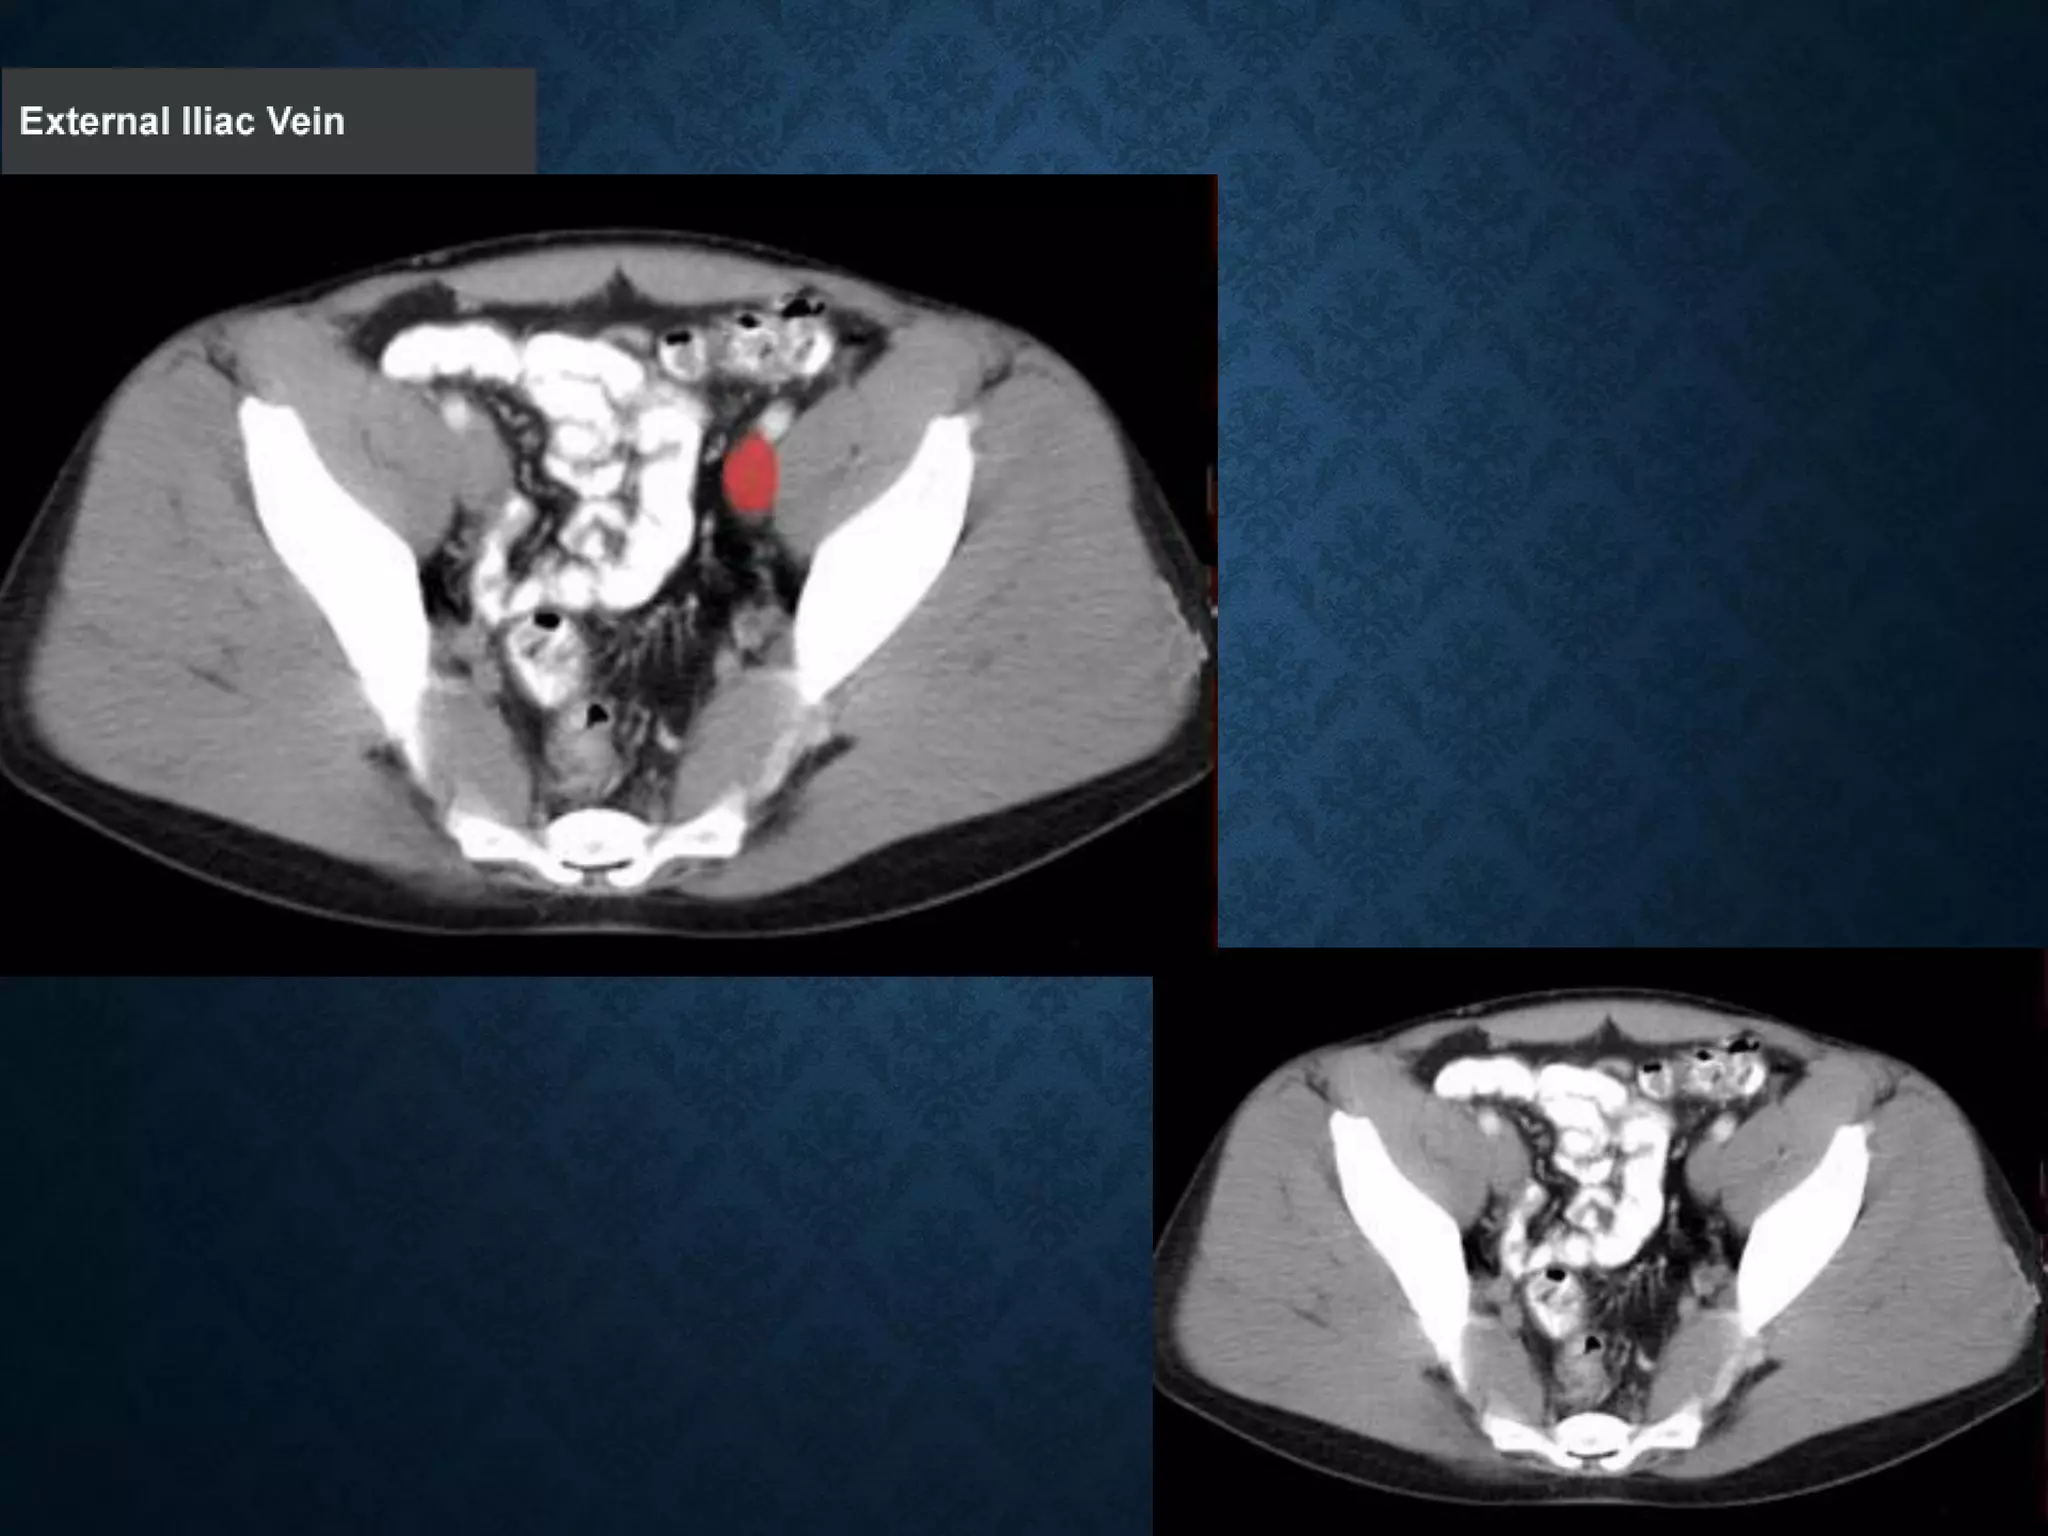

Identify the following structures in the body CT to the right. To view the location of the structure in the image click on

the label at the left and the structure will be indicated in the image. Abdominal CT scans typically begin just above

the diaphragm, so the first slice you see is of the lower chest.

NORMAL ANATOMY- SECTION 11